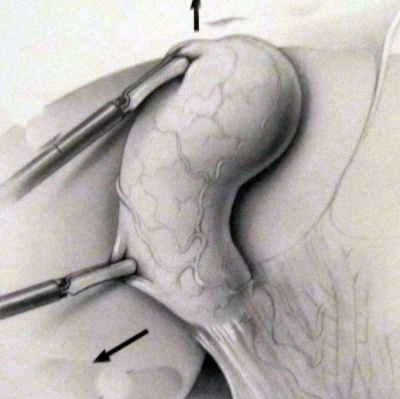

לאחר שמזהים את כיס המרה בעזרת תופס כיס המרה, דוחקים את כיס המרה מעל לכבד, וכך הוא נשאר במשך כל הניתוח. צעד זה מאפשר זיהוי משופר של הציסטיקוס ועורק כיס המרה. בעזרת תופס כיס המרה השני תופסים את כיס הארטמן, ובעזרתו מושכים את כיס המרה וחושפים אותו (איור 8.8 ו- 9.8).

כעת יש לפתוח את הצפק בבסיס כיס המרה ולחשוף את צינור המרה ואת עורק המרירה (איור 10.8). בעזרת מכלב יש "לקשור" את עורק כיס המרה ואת צינור כיס המרה ולנתקם.

| איור 10.8: חשיפת הציסטיקוס (תמונה עליונה) וסגירת צינור כיס המרה על-ידי מכלב (תמונה תחתונה). |